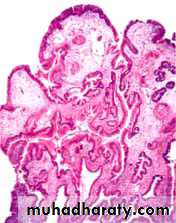

The majority of inflammatory or hyperplastic polyps are smaller than 1 cm in diameter and are frequently multiple, particularly in individuals with atrophic gastritis.Microscopically, polyps have irregular, cystically dilated, and elongated foveolar glands .

Gastric hyperplastic polyp. Low-power microscopic view of the polyp showing hyperplastic foveolar epithelium and inflammation.